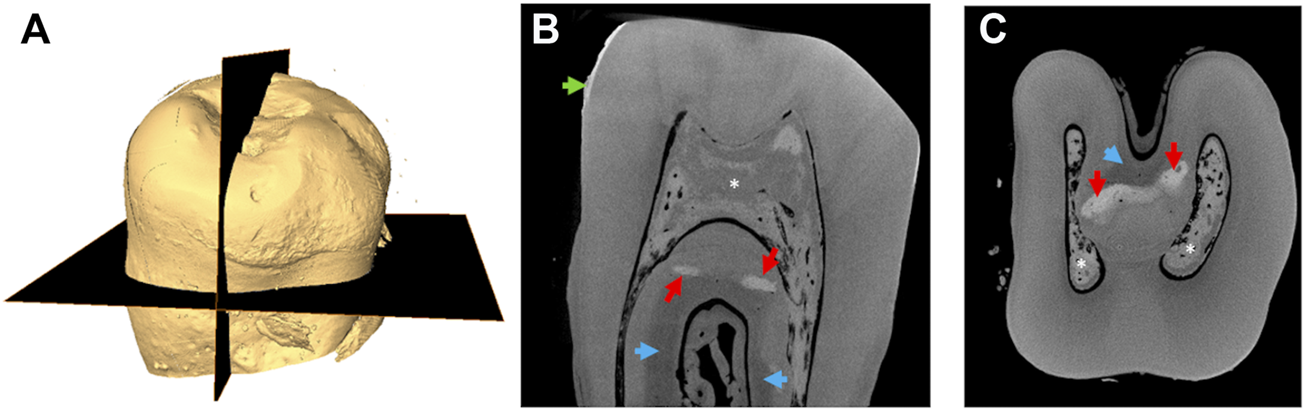

Figures 1A shows a representative 3D reconstruction of an unerupted ERS deciduous molar. The occlusal surface is almost flat due to the strong reduction in the thickness of the enamel layer clearly evidenced in Figures 1B. Although a distinguishable layer of enamel was seen, its mineralization level (enamel grayscale) appeared low in both sagittal and transverse sections (Table 1). The pulp chamber and root canals were filled with a radiopaque calcified material (Figures 1B,C). Areas of altered dentin grayscale indicating zones of hyper- or hypo-mineralization (arrows in Figures 1B,C, Supplementary Figure S1) were also observed and essentially located near the interradicular space.

FIGURE 1. Micro-CT images of an ERS tooth (A) 3D reconstruction based on μ-CT imaging; the planes analyzed are shown in black. (B) Gray shade micro-CT image from a sagittal section (vertical black plane of A). (C) Gray shade micro-CT image from a transverse section (horizontal plane of A). The red arrows indicate zones of increased mineralization. The blue ones indicate hypomineralized zones. The green arrow indicates pseudo enamel layer. Asterisks indicate calcifications in the pulp.